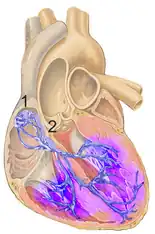

| An illustration of a right bundle branch block located in intraventricular septum | |

A right bundle branch block (RBBB) is a heart block in the right bundle branch of the electrical conduction system.[1]

During a right bundle branch block, the right ventricle is not directly activated by impulses travelling through the right bundle branch. The left ventricle, however, is still normally activated by the left bundle branch. These impulses are then able to travel through the myocardium of the left ventricle to the right ventricle and depolarize the right ventricle this way. As conduction through the myocardium is slower than conduction through the bundle of His-Purkinje fibres, the QRS complex is seen to be widened. The QRS complex often shows an extra deflection that reflects the rapid depolarisation of the left ventricle followed by the slower depolarisation of the right ventricle.